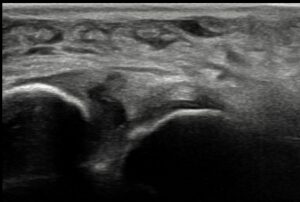

これまでのものより画質が良く、より細かな描出ができるようになりました。

手首の骨折(橈骨遠位端部骨折)

手首の腱鞘炎

足首の靭帯断裂

鎖骨骨折(10日後)

野球肘